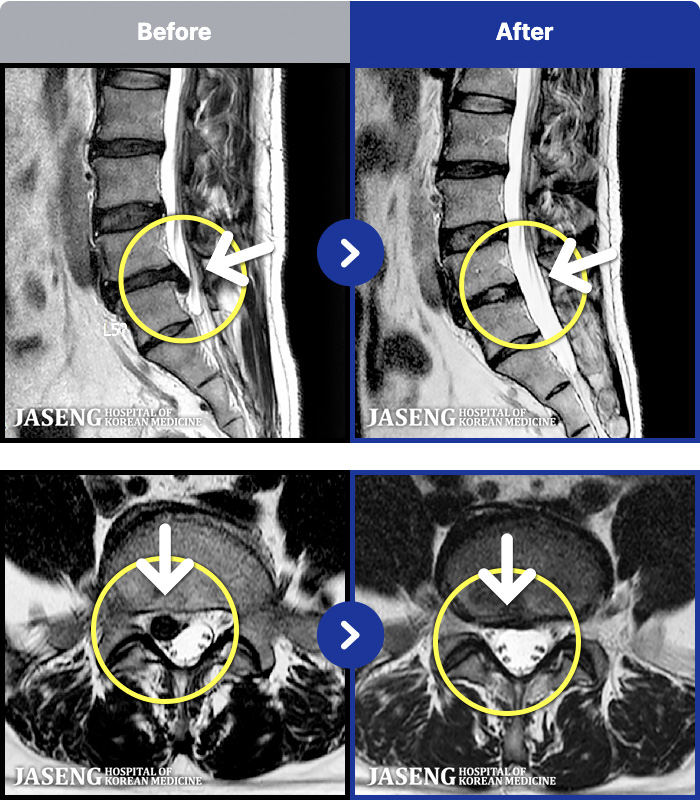

허리디스크

도움받은 사례

분당 · 신재권 원장

통증으로 아기를 안지 못하던 여자분입니다

촬영시기

2023.11.08 ~ 2024.07.29

2024.08.14